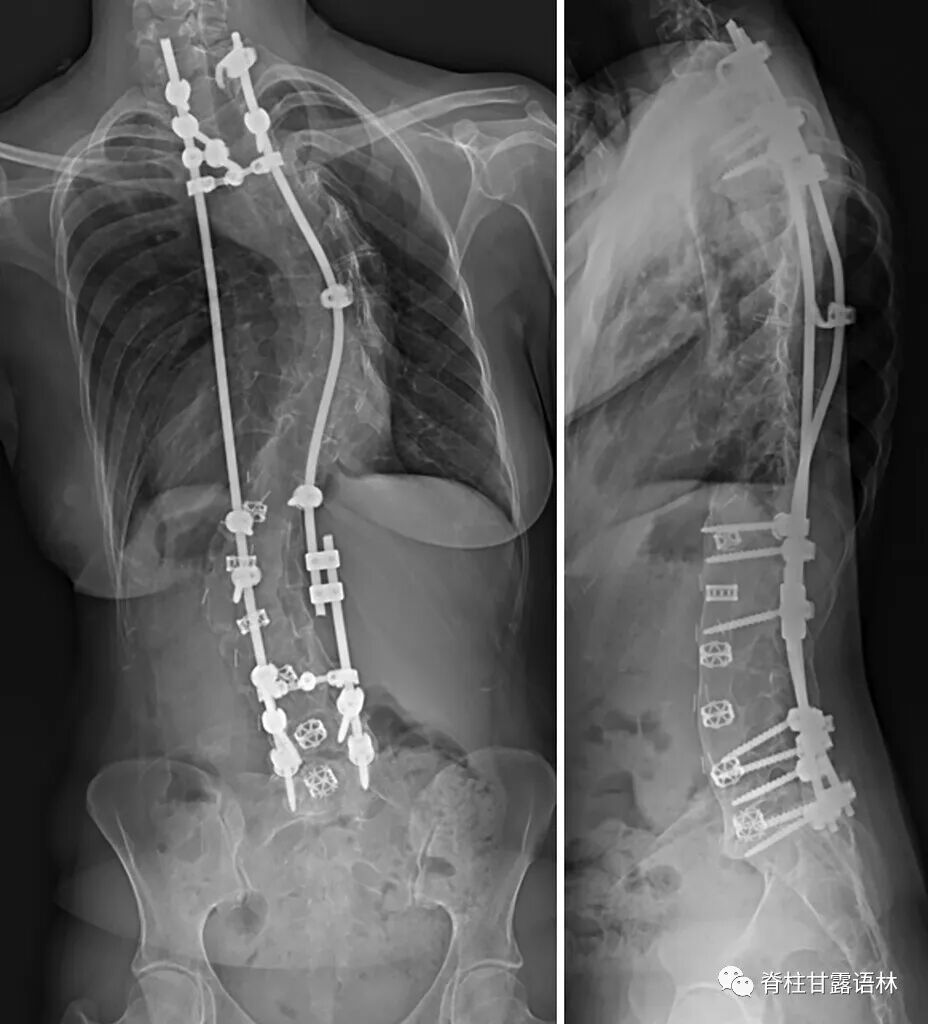

25岁时她回到诊所复查,当时她没有任何症状,否认存在背痛、腹痛、麻木、无力或步态障碍。检查时,她双侧上肢和下肢的力量和感觉完全正常。下肢血管检查显示双侧足背肌和胫后脉搏正常。站立的全脊柱X光片显示内固定无松动断裂或近端交界区后凸畸形。可观察到残余的胸腰段脊柱侧弯伴有凸起的右侧胸廓曲线和代偿性左下骨盆倾斜(图 1)。CT扫描可观察到右侧T12椎弓根螺钉尖端超出T12椎体皮质前缘5mm,进入右后外侧主动脉壁,没有血肿或假性动脉瘤的证据(图 2 )。尽管主动脉内的椎弓根螺钉尖端在临床上仍无症状,且在影像学上没有进展,但患者和她的家人选择继续进行手术干预以防止将来可能出现的并发症。

图1 修复手术前获得的前后位(左)和侧位(右)脊柱侧弯X光片。